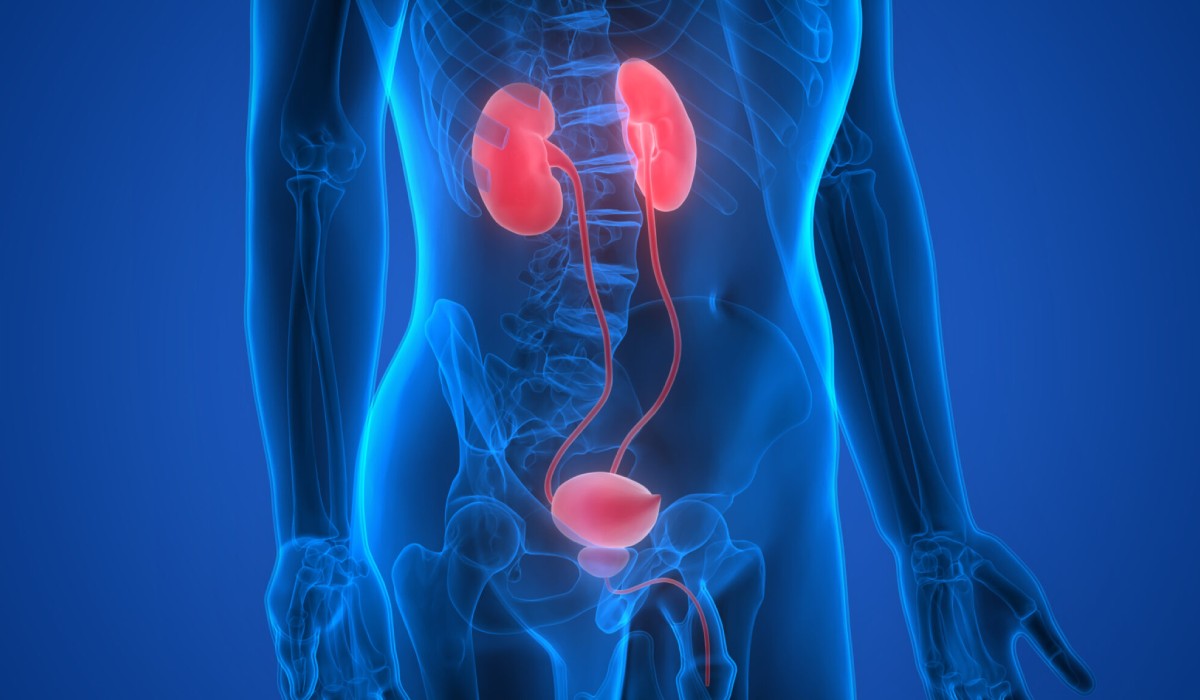

"I had an excellent experience at the urology clinic. The staff was very friendly and professional, and the doctor was knowledgeable and thorough in their examination. I received the care and attention I needed to address my urological concerns, and I highly recommend this clinic to anyone seeking quality